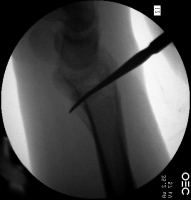

| Percutaneous

fracture stabilization with three pins via the

dorsal radial tubercle, radial styloid and FCR

portals. |

| Pins were left

protruding and bent to overlap. |